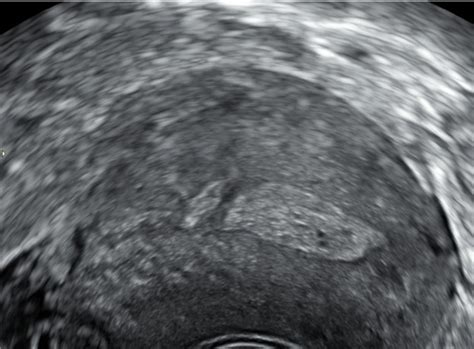

Diagnoza hematoma se običajno postavi na podlagi kliničnega pregleda, kjer zdravnik opazi oteklino, spremembo barve kože (modrica, rdečina) in lahko zatipa zatrdlino. V nekaterih primerih, zlasti če je hematom večji ali povzroča težave, se lahko uporabi ultrazvok (UZ) za potrditev diagnoze in oceno velikosti ter vsebine hematoma. V enem od primerov je ultrazvok pokazal tekočino v maternici, ki je bila diagnosticirana kot vnetje, kar lahko včasih spremlja tudi nastanek hematoma ali podobnih zapletov.